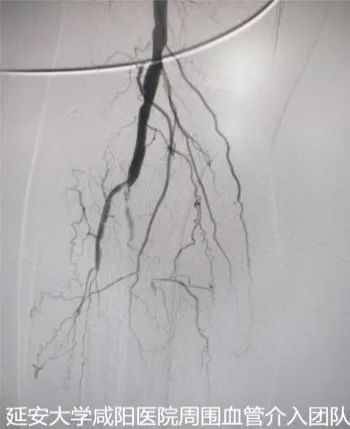

術前DSA

為了保肢,輾轉至我院心血管內科一病區(qū),吳棟梁副院長帶領周圍血管病介入團隊討論、經評估及術前準備后于3月24日對患者進行下肢動脈球囊擴張成形術,術中下肢動脈造影提示膝下脛前、脛后、腓動脈動脈閉塞,血管鈣化嚴重及側支血管形成較差(股腘動脈病變TASC II分型為D型);手術難度較大,手術失敗患者直接面臨截肢,在規(guī)范化的介入操作下最終開通患肢閉塞血管,術后肢體缺血癥狀立即改善,足背動脈搏動恢復;下肢變暖了,疼痛消失了,老爺子及家屬終于舒展開了愁眉,露出了久違的笑容。